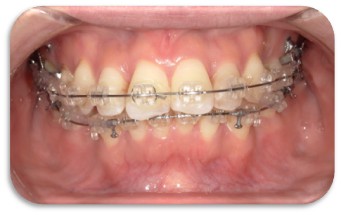

歯科クリニック中村は、むし歯や歯周病治療はもちろん、難しい親知らずの抜歯等の口腔外科、全体的な歯列矯正(マルチブラケット矯正やマウスピース矯正にも対応)、小さなお子さんへの小児矯正、また大学病院レベルのインプラント治療や審美治療、訪問診療まで多岐に渡り様々に対応しております。

日本成人矯正歯学会会員でもある、副院長がお子さんから大人までの歯並びにも対応しているため一つのクリニックで治療を完結することができます。